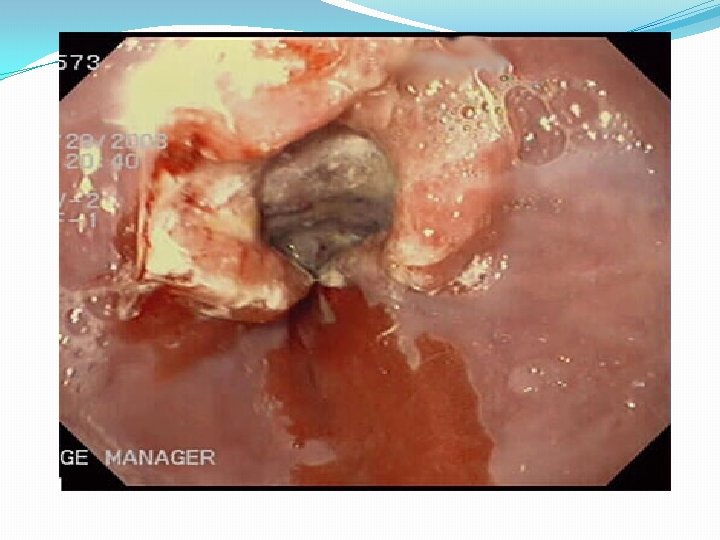

4. Endoscopy : allows diagnosis of erosive esophagitis and complications such as strictures or Barrett esophagus; biopsies can be taken. 5. Laryngotracheobronchoscopy : posterior laryngeal inflammation and vocal cord nodules. 6. Empirical antireflux therapy

Complications of GERD 1. Esophageal *Esophagitis and Stricture. * Barrett Esophagus *Adenocarcinoma 2. Nutritional: failure to thrive because of caloric deficits.